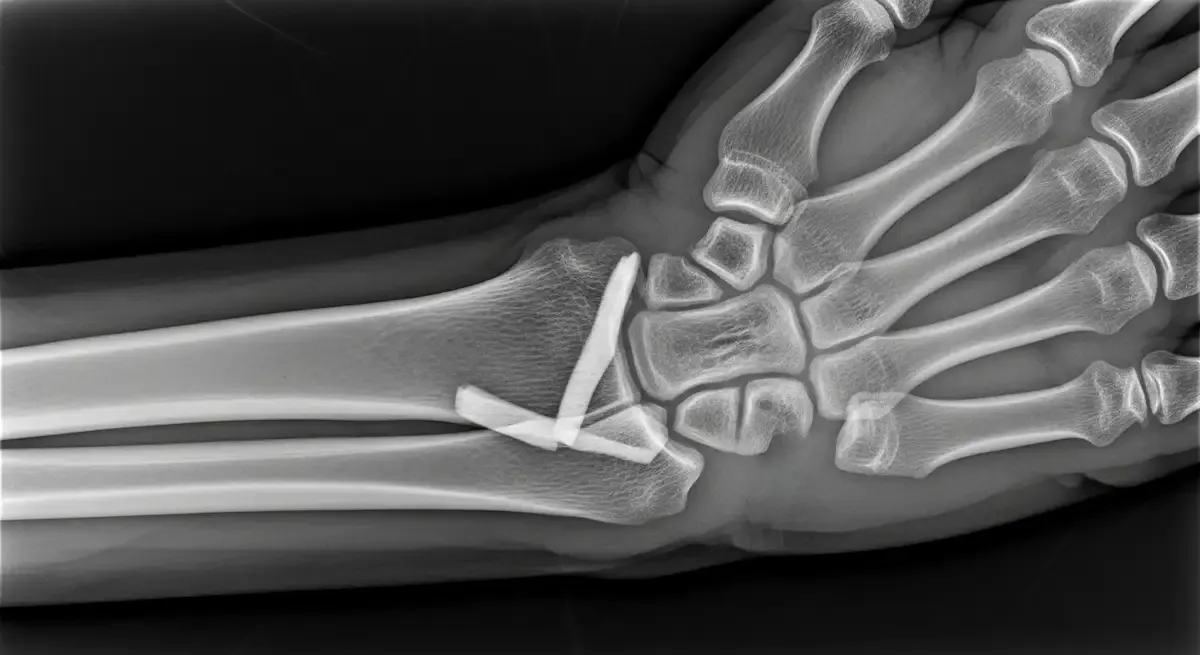

fraturas

Artigos sobre fraturas pelo Dr. Henrique Bufaiçal.